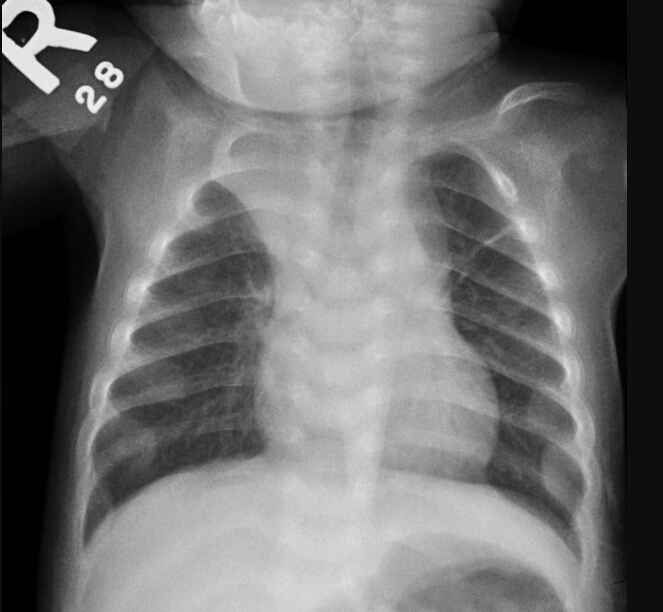

What is the diagnosis?

rib fracture